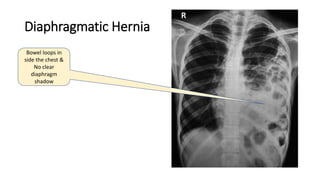

Diaphragmatic Hernia

Bowel loops in

side the chest &

No clear

diaphragm

shadow